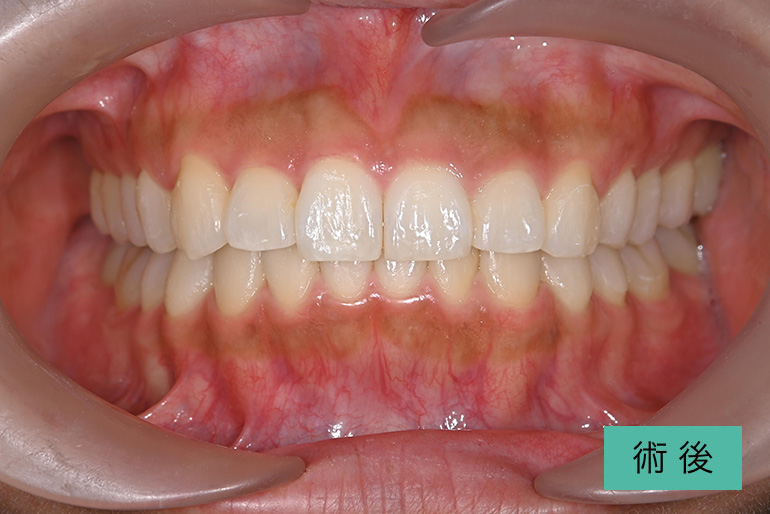

オールセラミック②

| 治療内容 | 上顎前歯右上3番から左上3番のセラミック冠 |

| 治療期間・回数 | 約1ヶ月、3回 |

| 費用(税込) | ¥990,000(165,000/1本)(補綴費用) ※自由診療 |

| リスク・副作用 | 疼痛、補綴物の脱落、咬合違和感、破折 |